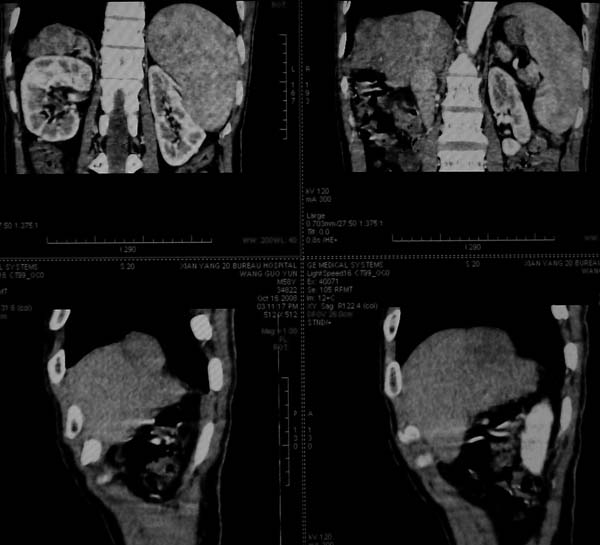

标题: CT16292:男,53岁,上腹部不适2月,B超发现肝内占位病变。 [打印本页]

标题: CT16292:男,53岁,上腹部不适2月,B超发现肝内占位病变。

肝脏体积变小,肝裂增宽,分布异常,肝尾叶增大,脾肿大,考虑肝硬化可能性大,右肝病灶呈现早期充盈,延迟强化考虑肝内胆管细胞癌可能,不除外血管瘤

肝叶比例失调,左叶增大,肝裂增宽,脾脏增大,门脉增宽,肝右叶包膜下多发结节样阴影,增强虽说强化幅度不大,但还是符合快进快出特点;考虑肝硬化、脾大、结节型肝癌。胆管细胞癌多有延时强化、肝包膜凹陷征、周围胆管扩张等特点,本例明显不符;故不考虑。

动脉期静脉有显影 是否静脉有受侵改变啊